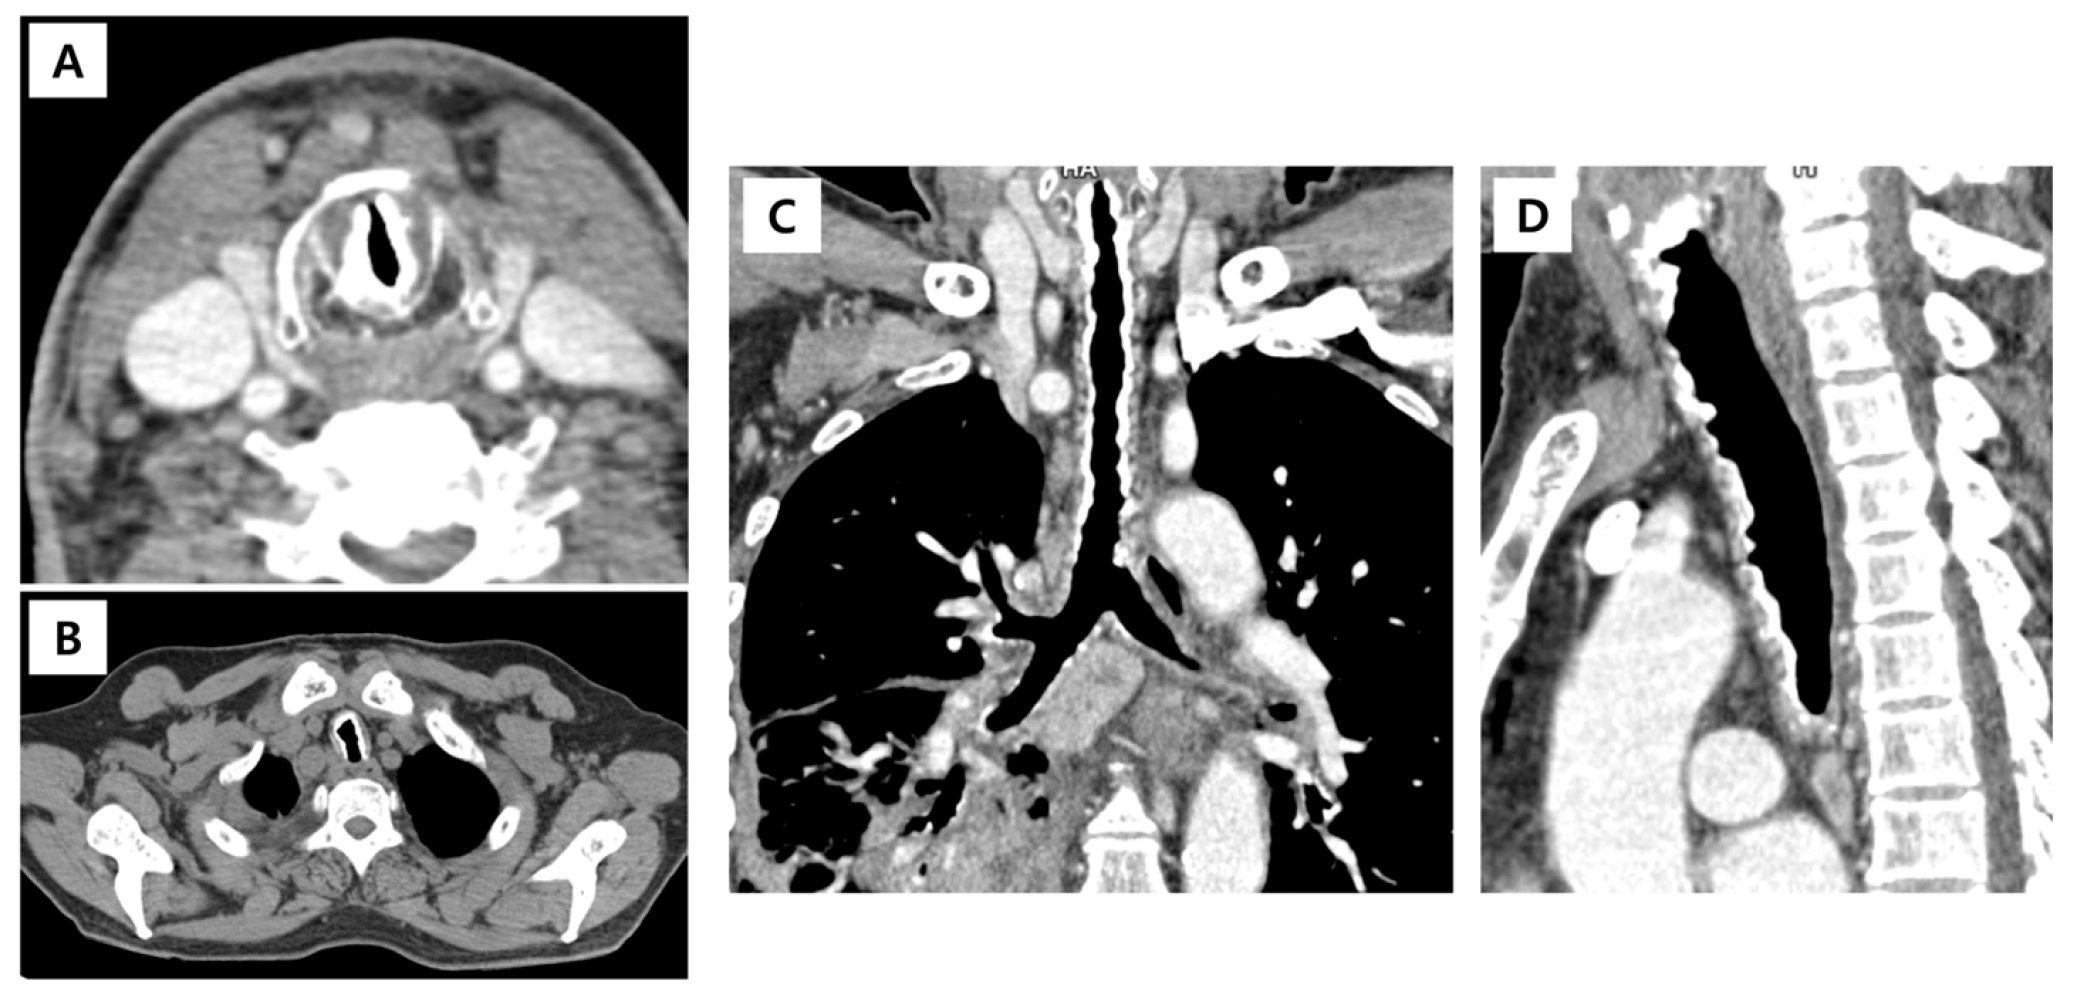

| Danckers (2015) | 27-year-old male | Acute hypercapnic respiratory failure; subglottic mass with cystic and solid component obstructing 75% of the airway | Intubation, mechanical ventilation; surgical drainage; prophylactic tracheostomy; antibiotics | Asymptomatic after tracheostomy removal; persistent vocal cord fixation | [6] |